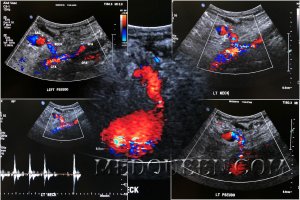

Под понятием «ложная аневризма» следует подразумевать скопление крови вне сосуда, сообщающееся с артерией через шейку, что приводит к завихрению кровотока внутри образования с характерной картиной на цветовой допплерографии. Исследование пульсовых волн ложной аневризмы показывает приносящий кровоток высокой скорости в момент систолы и длительный отток на протяжение всей диастолы (фото 1).

УЗИ: Ложная аневризма общей бедренной артерии

Фото 1. Ложная аневризма общей бедренной артерии. А – цветовая допплерограмма паховой области, выполненная в поперечной проекции: визуализируется общая бедренная артерия (CFA), стрелкой отмечена шейка аневризмы, указателями отмечена ложная аневризма, локализованная спереди, в которой наблюдается типичная картина «инь-янь» красного и синего цвета, что обусловлено завихрением кровотока. В – спектральная допплерограмма шейки ложной аневризмы подтверждает кровоток в обе стороны («туда-сюда»).

Допплерографическое исследование позволяет диагностировать ложную аневризму при обнаружении в ее шейке потока по типу «туда-сюда» (компонент «сюда» обусловлен расширением полости ложной аневризмы по мере вхождения в нее крови в систолу; компонент «тужа» отмечается в диастолу, когда кровь, накопившаяся во время диастола, возвращается обратно в артерию (фото 1).

Признаки ложной аневризмы на цветовой допплерографии характеризуются классическим двунаправленным потоком внутри капсулы аневризмы при каждом сердечном цикле – симптом «инь-янь».